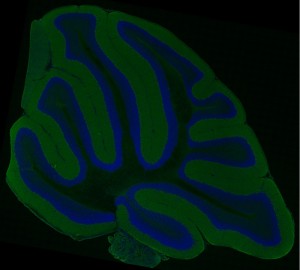

A high resolution multiphoton microscopy mosaic image of a cerebellar distribution of cell bodies (Hoescht 33342; blue) and alpha-synuclein (green) from a non-transgenic animal.

This large scale image was acquired using a customized RTS2000 multi-photon microscope (Fan et al., 1999) equipped with a custom automated high precision motorized stage (Applied Precision LLC, Issaquah, WA, USA), which allows for the automatic acquisition of ultra-large field image mosaics in 2 and 3 dimensions (Price et al., In Press; Chow et al., Submitted). A Nikon Plan Apo TIRF (60X 1.45) oil immersion objective was used. These mosaic images are acquired by rastering the specimen along the X, Y, and Z axes, introducing a prescribed amount of overlap between acquired images (in this case 10%) to aid alignment. Unprocessed data acquired on the RTS2000 microscope is subsequently stored as a single stack of images. The image stack is analyzed using the JAVA-based ImageJ, a freely available software package, using plugins developed at NCMIR for processing, aligning, and assembling these massive datasets. Briefly, each file is separated into three separate .tiff stacks, one for each channel. Each tile is normalized to eliminate shading gradients, followed by the automatic alignment of individual tiles to form a full size mosaic image of the data for each channel. A globally optimized, accuracy. The assembled mosaics are then combined into one full-scale color image. For 3D imaging, the process is repeated for each wide field image plane in Z. The resulting image mosaics provide detailed views of cellular and subcellular structure and macromolecular distributions in a larger tissue context. These maps are being used to characterize Parkinson’s Disease. These data will provide the bridge between whole brain imaging techniques such as MRI (Duke University, CIVM) and electron microscopic (UCSD-NCMIR) analysis.